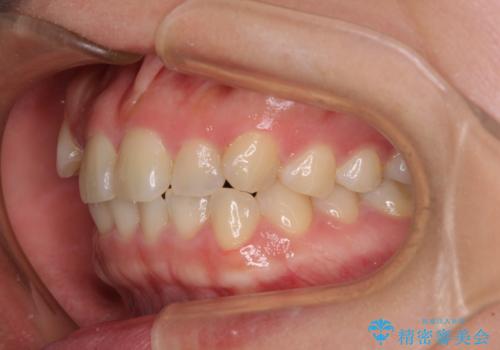

八重歯を治す 非抜歯のワイヤー矯正治療

- 左右の八重歯を気にして来院された患者様です。

ワイヤー装置でもマウスピースでも対応可能な歯列でしたが、マウスピース矯正は自己管理が煩わしいとのことでワイヤー矯正を選択されました。

八重歯である犬歯は歯根が長いため、上顎前歯が出っ歯になるリスクがあるため、必要に応じてアンカースクリューを用いて奥歯を後方に移動させる可能性をお伝えしました。